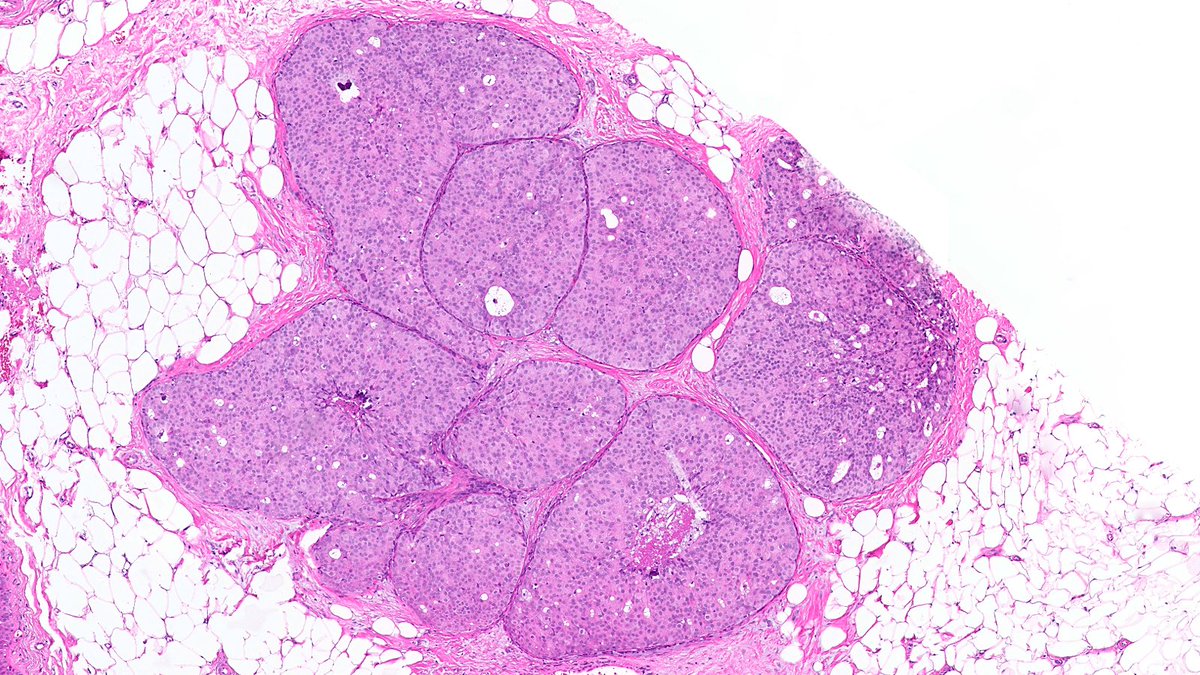

Adult male. Retroperitoneal mass. #PathX #PathTwitter #BSTPath

SumantaDas_7's tweet image. Adult male. Retroperitoneal mass.

#PathX #PathTwitter #BSTPath